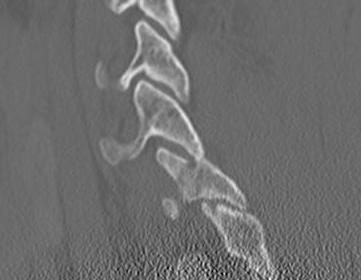

Superior articular process fracture

- potentially unstable

Inferior articular process fracture

- thought to be more stable